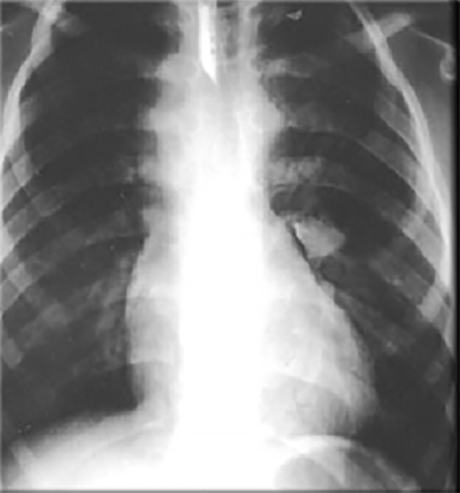

This chest X ray shows right ventricular hypertrophy, a small pulmonary trunk and decreased pulmonary arterial vascularity.

Right ventricular hypertrophy is suggested by the

upturned cardiac apex.

A small pulmonary trunk is suggested by the

absence of cardiac density beneath the aortic knob, resulting in a straight edge of the upper left cardiac silhouette.

Decreased pulmonary arterial vascularity is suggested by the small size of the central pulmonary arteries shadows and absence of distal arterial markings. This chest X ray is consistent with tetralogy of Fallot.